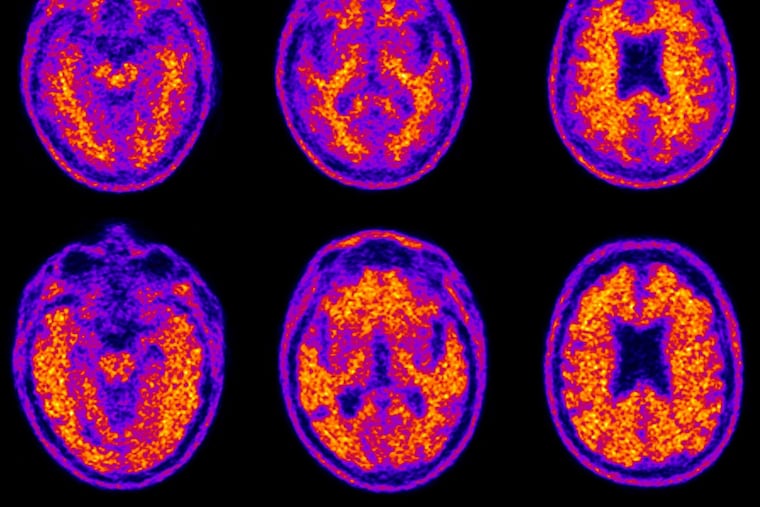

Could Alzheimer’s be an autoimmune disease? New research says it’s not just about the brain.

My laboratory at the Krembil Brain Institute, part of the University Health Network in Toronto, is devising a new theory of Alzheimer’s disease. Based on our past 30 years of research, we no longer think of Alzheimer’s as primarily a disease of the brain. Rather, we believe that Alzheimer’s is principally a disorder of the immune system within the brain.